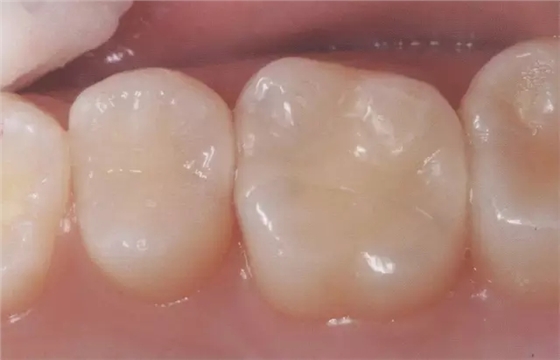

圖2右5進行了全瓷嵌體修復,為了使受力均勻,線角需要呈圓弧狀。